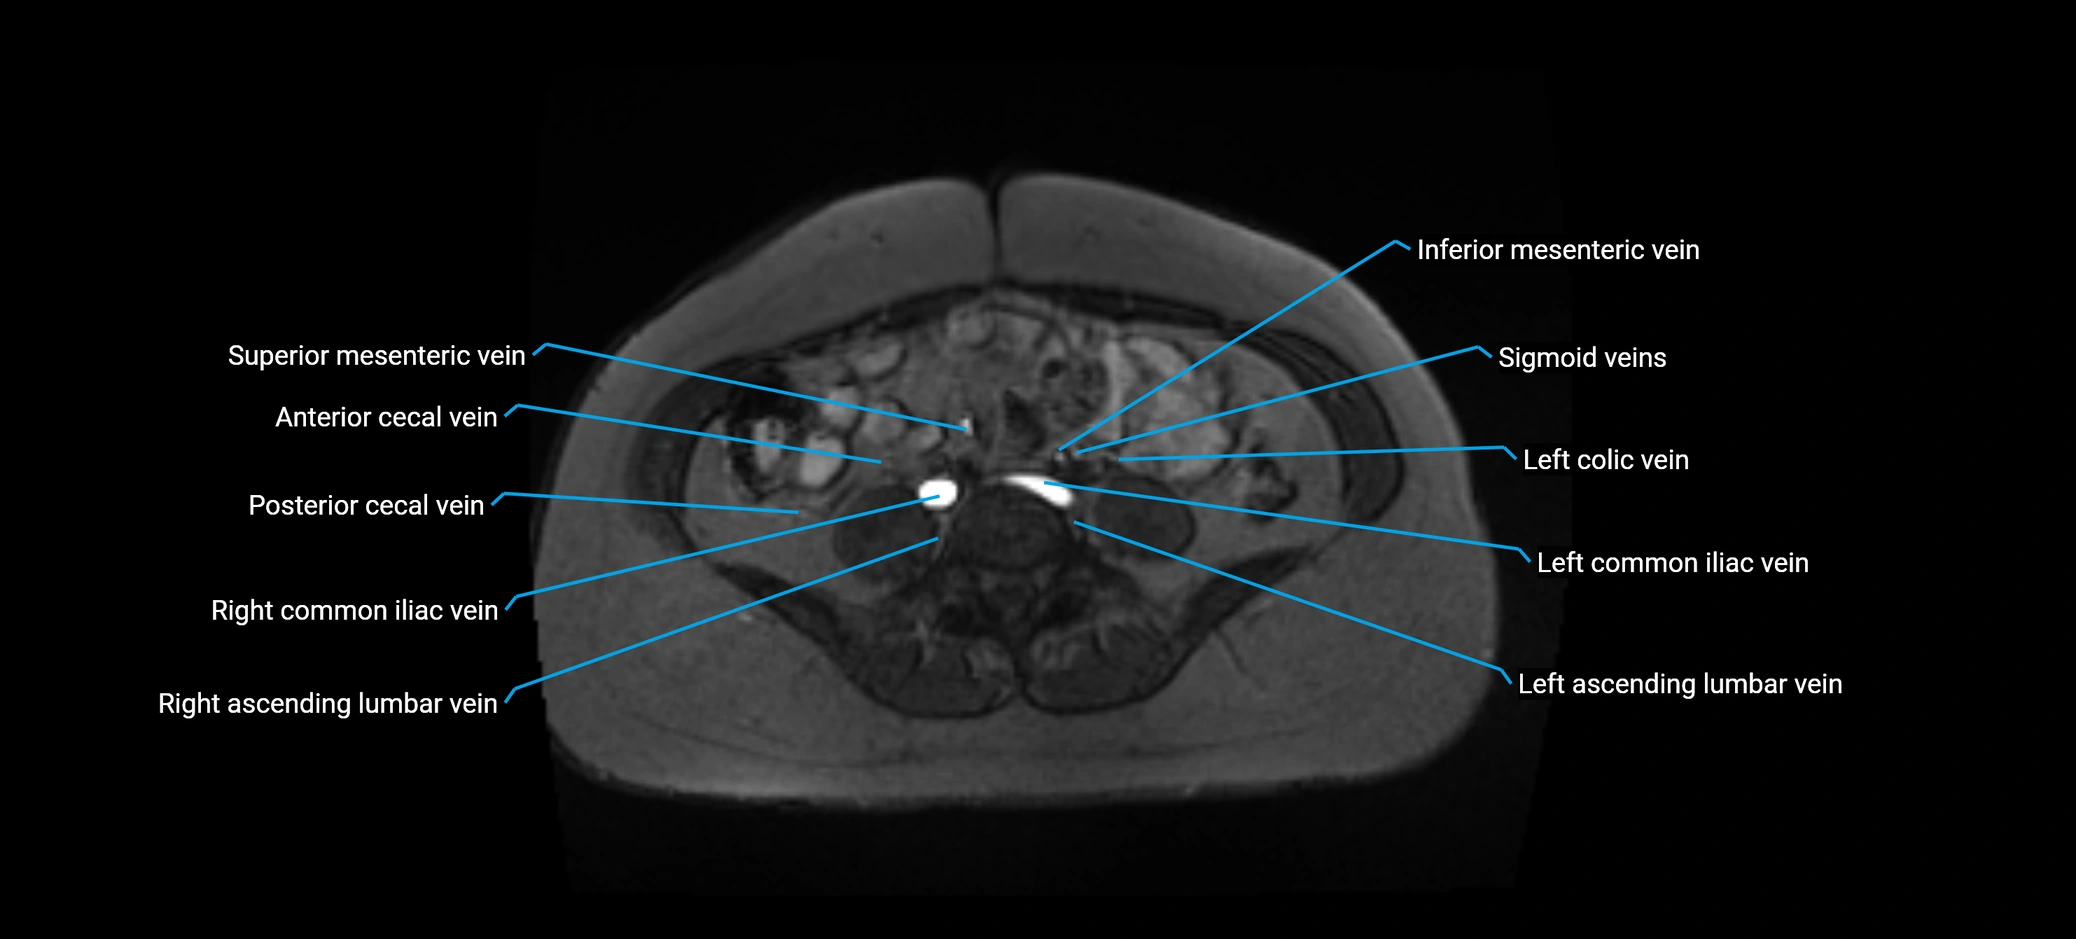

MRI image

image